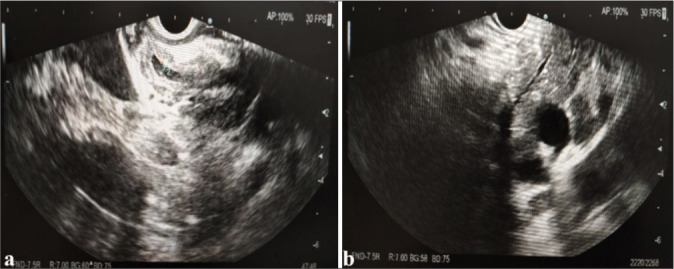

Objective: Histopathology examination is important for diagnosing autoimmune pancreatitis (AIP), which is suspected to be pancreatic cancer based on imaging findings. Although the validity of endoscopic ultrasound-guided fine-needle aspiration (EUS-FNA) in the diagnosis of AIP is still debated globally, this study aimed to evaluate the efficacy of EUS-FNA in the diagnosis of AIP with suspected pancreatic cancer.

Material and methods: From January 2021 to June 2024, 30 AIP patients with radiographically diagnosed pancreatic cancer were enrolled and underwent EUS-FNA. Sex, age, symptoms, CA199, serum immunoglobulin G4 (IgG4), and treatment outcome were included. Tissue sampling conditions, puncture sites, storiform fibrosis, CD38- and IgG4-positive plasma cell counts, and obliterans phlebitis were evaluated.

Results: Thirty patients, 24 males and six females, with an average age of 60.53 ± 11.72 years (32-79 years), were included in the study. Thirty patients had their serum IgG4 and CA199 levels tested. Tissue samples containing ≥10 were obtained from 19 (63.33%) patients. CD38+ plasma cell infiltration and laminar fibrosis were detected in 22 (73.33%) and 10 (33.33%) patients. According to the International Consensus Diagnostic Criteria ( ICDC), 12 patients had histopathological levels of Grade 1, 15 of Grade 2, and three patients could not be classified. The accuracy, sensitivity, and specificity of EUS-FNA in diagnosing AIP with suspected pancreatic cancer on imaging were 96.66% (29/30), 96.42% (27/28), and 100% (2/2), respectively. The area under the curve value of EUS-FNA for patients with AIP who were radiologically suspected of having pancreatic cancer was 0.957.

Conclusion: Approximately 90% of patients with EUS-FNA results are diagnosed with an ICDC level of 2 or higher. Our results suggest that for cases where malignant tumors are suspected after imaging or cannot be ruled out, obtaining pancreatic tissue through EUS-FNA puncture for pathological diagnosis is recommended.